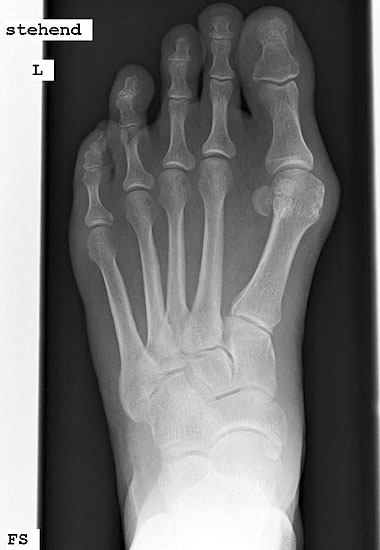

Röntgenaufnahme des Fußes im Stehen im dorsoplantaren und seitlichen Strahlengang (Abb. 1a-b).

Beurteilung des ersten Intermetatarsalwinkels (IMA), des Hallux valgus Winkels (HVA), des distalen (Distal Metatarsal Articular Angle, DMAA) und proximalen Gelenkflächenwinkels der Grundphalanx (Proximal Phalangeal Articular Angle, PPAA).

Abbildung 1a

Abbildung 1b